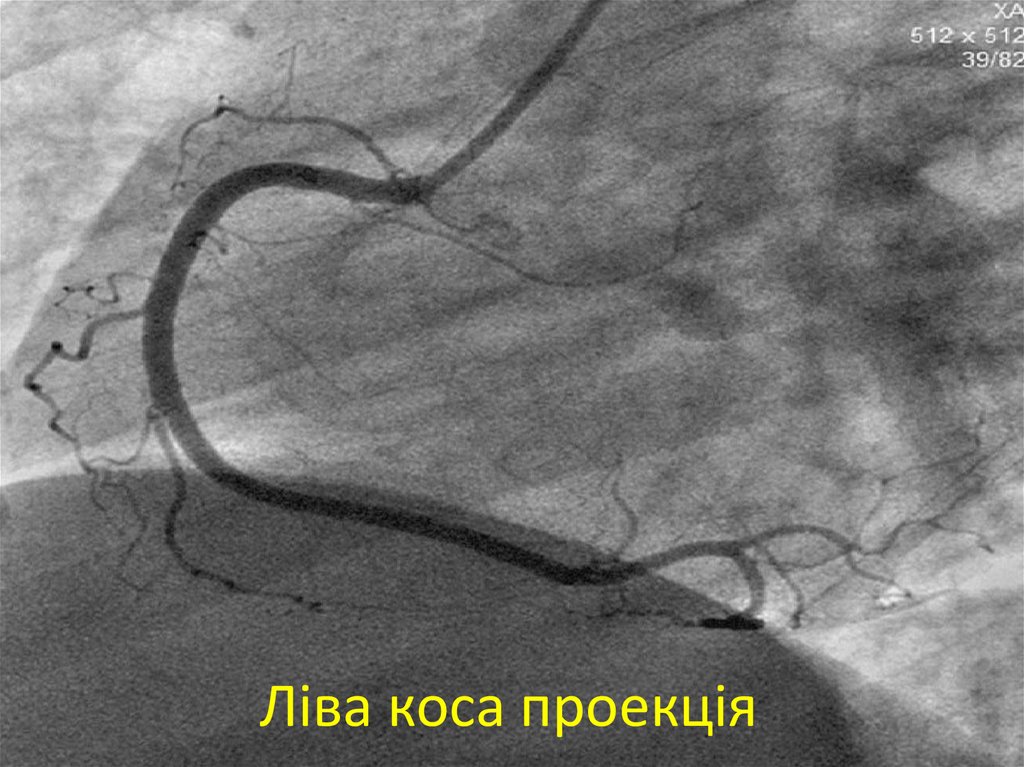

31. Ліва коса проекція

32. Ліва коса проекція

33. Ліва коса проекція